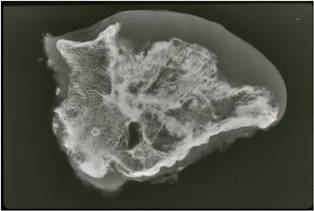

Gross Pathology

- The osteochondroma is completely covered in periosteum

- Cut surface shows hyaline composition of cartilage cap

Cap

- Younger patients thicker cap because of growth hormone

- Smooth or knobby

- 2 mm to 1 cm thick

Beneath the cap, calcified cartilage which appear as white deposits are present